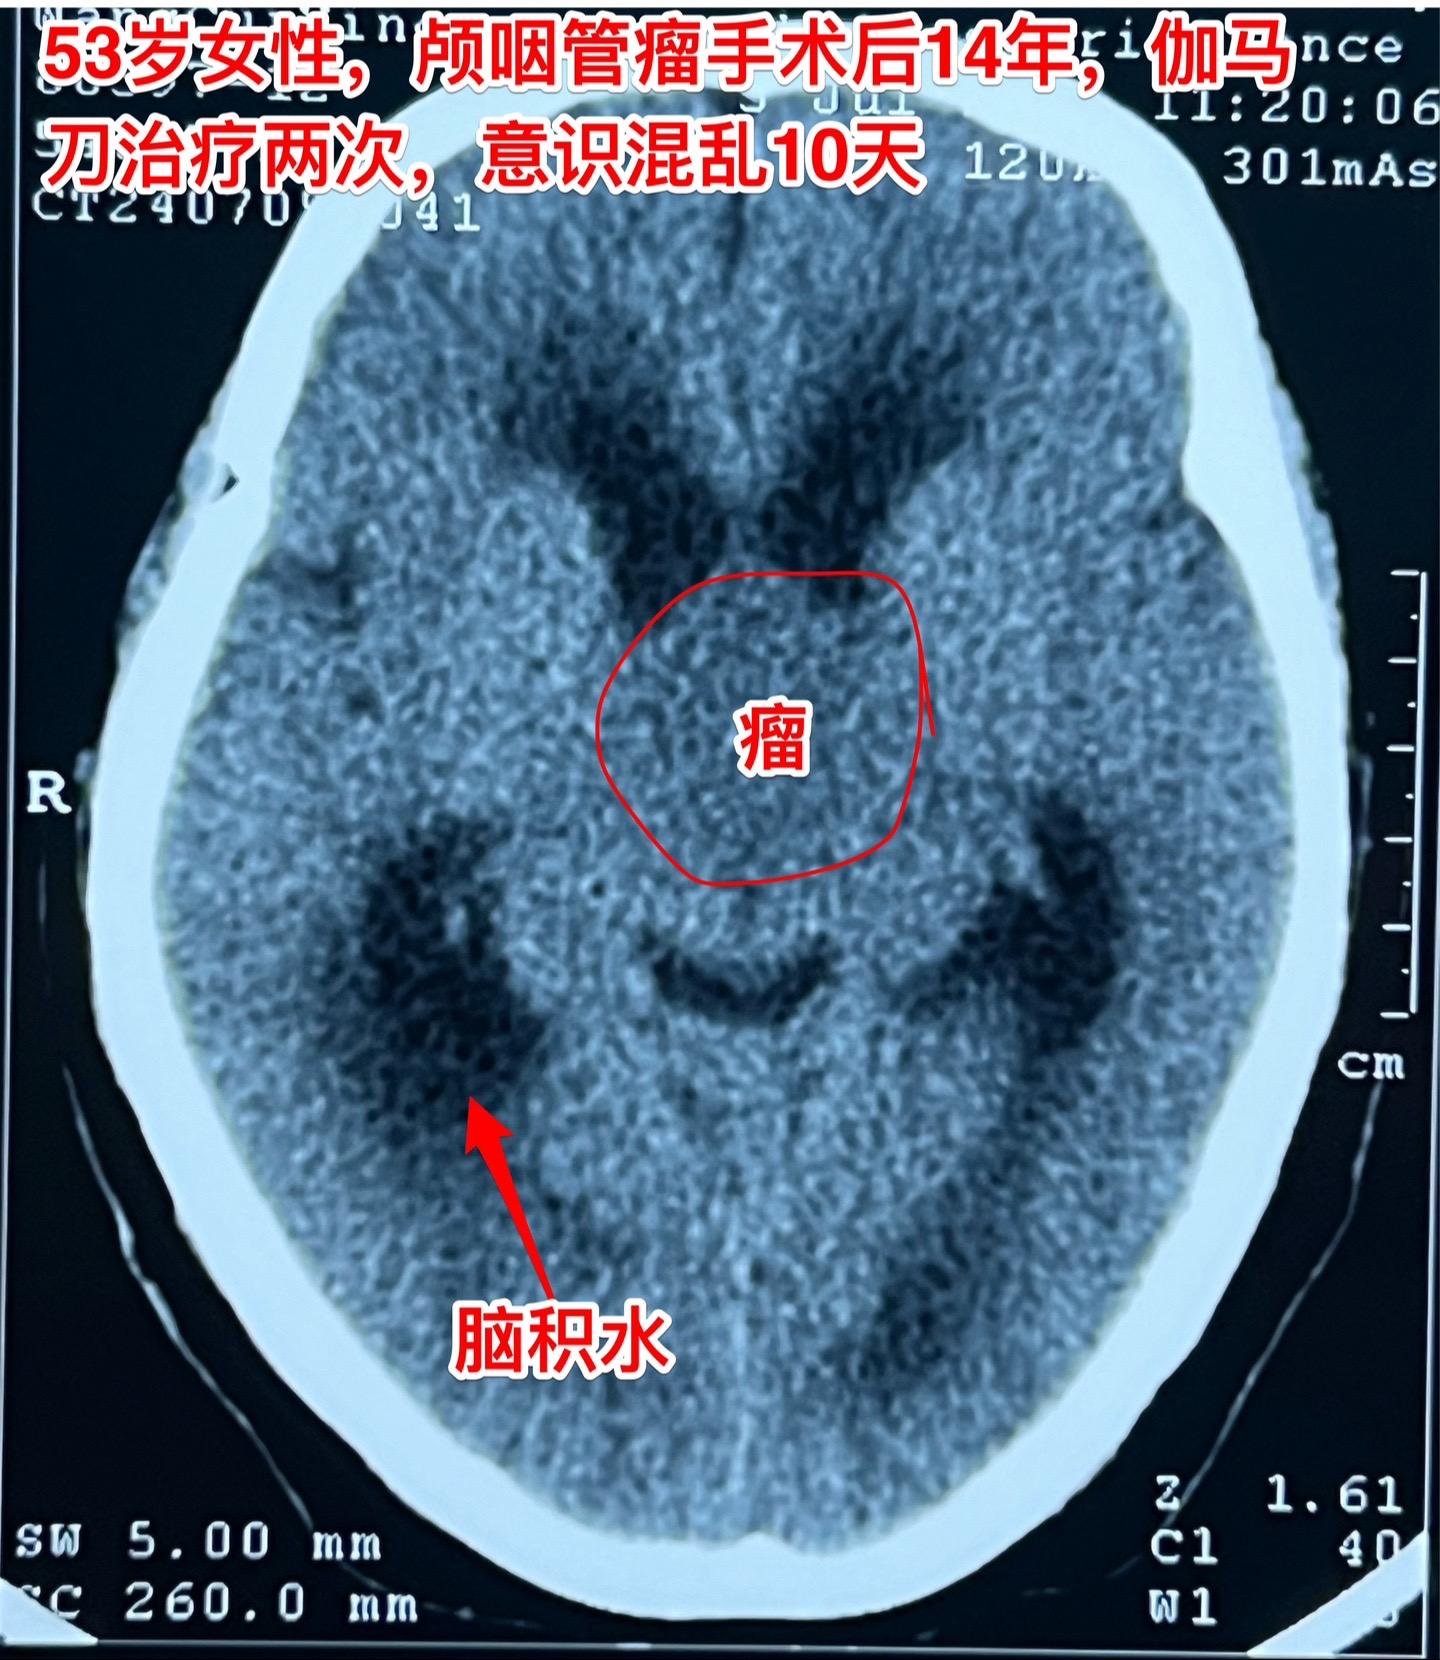

颅咽管瘤复发了怎么就意识混乱了?安徽省宿州的女性,53岁,14年前曾经作过颅咽管瘤切除手术。近10天她突然出现意识混乱,胡说,尿失禁,行走不稳。这是为什么呢? 其实她的病并不突然。 14年前作过颅咽管瘤切除手术,肿瘤有残留,就作了伽马刀治疗。2015年肿瘤复发了,又作了一次伽马刀治疗。之后生活质量还不错,能够作家务。 住院前10天她突然出现意识混乱,胡言乱语,同时还有尿失禁,行走困难。到医院去作头C T检查,发现肿瘤复发了,而且还造成了脑积水。